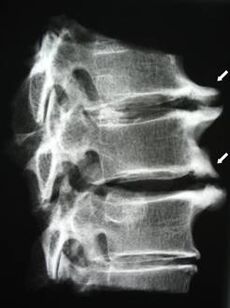

Im Frühstadium wird Osteochondrose mittels MRT erkannt. Anschließend kann die Pathologie durch Röntgen diagnostiziert werden. Auf Röntgenaufnahmen der Halswirbelsäule fallen eine Verringerung des Wirbelabstands, pathologische Veränderungen der Wirbelgelenke und eine Osteophytose auf.

| Zervikale Osteochondrose | Das Auftreten pathologischer Veränderungen in einem oder mehreren Bewegungssegmenten der Wirbelsäule. Beeinträchtigte Beweglichkeit der Wirbelsäule, Entwicklung myofaszialer Schmerzsyndrome und Einklemmen der Wirbelsäulenwurzeln | Schmerzen, Parästhesien und motorische Störungen im Halsbereich, die sich bis zum Hinterkopf und den oberen Gliedmaßen erstrecken. Erkennung charakteristischer Veränderungen der Wirbelsäule im MRT und Röntgen (Osteophyten, Verringerung des Wirbelabstands, Anzeichen einer Schädigung der Zwischenwirbelgelenke) |